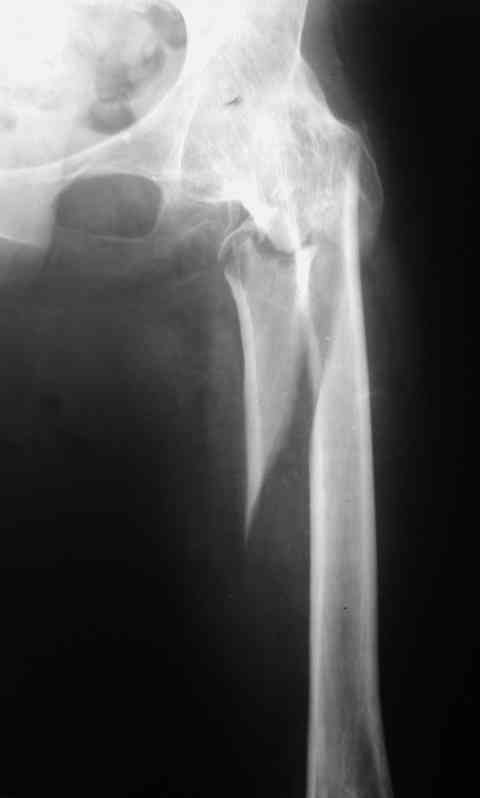

Рентгенограммы до и после. Больной профессор на кафедре сопромата и после детального изучения

особенностей имплантата, собственных рентгенограмм дал добро на операцию. Ваш вариант лечения вполне симпатичен.

С уважением А.Семенистый.